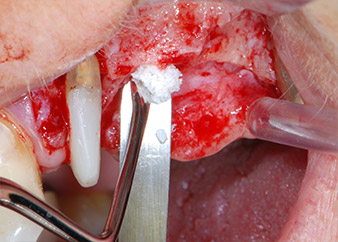

Antes de la colocación del implante y tras la verificación de que la membrana de Schneider estaba intacta (figura 9), la base interna del seno se aumentó en las dos posiciones del implante con un material sustituto de hueso xenógeno (Bio-Oss, Geistlich Biomaterials) (figura 10).

sonda-CPITN

Fig. 10: Se insertó un material sustituto de hueso xenógeno en la osteotomía del implante para el aumento interno del seno. El material se condensó con cuidado en dirección apical con la sonda CPITN con punta esférica (no mostrado).